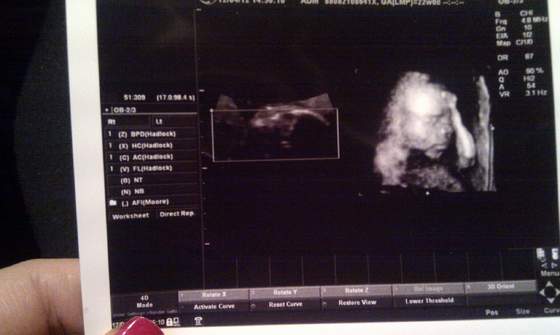

Dzidziuś pięknie wygląda, jest zdrowy, ruchliwy, ziewał sobie, pokazał pitoczka ze wszystkich stron (z tej okazji znów kupiłam dzisiaj kilka niebieskich ciuszków), nie wiem ile ma długości ale waży 310 gram, więc chyba do wielkoludów nie należy ale nie wiem bo się nie znam. Doktor mówił że wszystko jest ok, to znaczy że ok

oglądaliśmy wszystkie obszary mózgu, komory i przedsionki serca, oraz inne organy wewnętrzne. Najfajniej jednak wyglądały stópki :-)